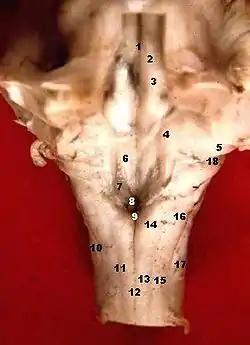

Rhomboid fossa

Rhomboid fossa.

The rhomboid fossa is a rhombus-shaped depression that is the anterior part of the fourth ventricle. Its anterior wall, formed by the back of the pons and the medulla oblongata, constitutes the floor of the fourth ventricle.

It is covered by a thin layer of grey matter continuous with that of the spinal cord; superficial to this is a thin lamina of neuroglia which constitutes the ependyma of the ventricle and supports a layer of ciliated epithelium.

The fossa consists of three parts, superior, intermediate, and inferior:

The superior part is triangular in shape and limited laterally by the superior cerebellar peduncle; its apex, directed upward, is continuous with the cerebral aqueduct; its base is represented by an imaginary line at the level of the upper ends of the superior foveae.

The intermediate part extends from this level to that of the horizontal portions of the taeniae of the ventricle; it is narrow above where it is limited laterally by the middle peduncle, but widens below and is prolonged into the lateral recesses of the ventricle.

The inferior part is triangular, and its downwardly directed apex, named the calamus scriptorius (as is shaped like a writing quill-nib)[1] is continuous with the central canal of the closed part of the medulla oblongata.

The sulcus limitans forms the lateral boundary of the medial eminence.

In the superior part of the rhomboid fossa it corresponds with the lateral limit of the fossa and presents a bluish-gray area, the locus coeruleus, which owes its color to an underlying patch of deeply pigmented nerve cells, termed the substantia ferruginea.

At the level of the facial colliculus the sulcus limitans widens into a flattened depression, the superior fovea, and in the inferior part of the fossa appears as a distinct dimple, the inferior fovea.

Lateral to the foveæ is a rounded elevation named the area acustica, which extends into the lateral recess and there forms a feebly marked swelling, the tuberculum acusticum.

Winding around the inferior peduncle and crossing the area acustica and the medial eminence are a number of white strands, the striæ medullares, which form a portion of the cochlear division of the acoustic nerve and disappear into the median sulcus.

Below the inferior fovea, and between the hypoglossal trigone and the lower part of the area acustica is a triangular dark field, the vagal trigone, which corresponds to the sensory nucleus of the vagus and glossopharyngeal nerves.

The lower end of the vagal trigone is crossed by a narrow translucent ridge, the funiculus separans, and between this funiculus and the gracile nucleus, is a small tongue-shaped area, the area postrema.

On section it is seen that the funiculus separans is formed by a strip of thickened ependyma, and the area postrema by loose, highly vascular, neuroglial tissue containing nerve cells of moderate size.